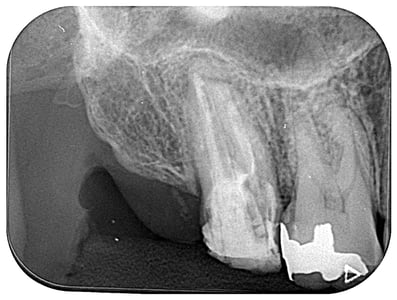

右上7番

根管内には、3本の破折ファイルの残存。それ以外は、多量の軟化象牙質(一部は髄床底穿孔)。根尖病巣の存在。対合歯とのクリアランス少なく、保存するにも補綴するには無理か?と思われましたが、約1年。月に1度。当院から片道2時間半、かけて通っていただき、無事に補綴に至りました。

これから矯正治療になりますので、まだまだ長い道のりです。